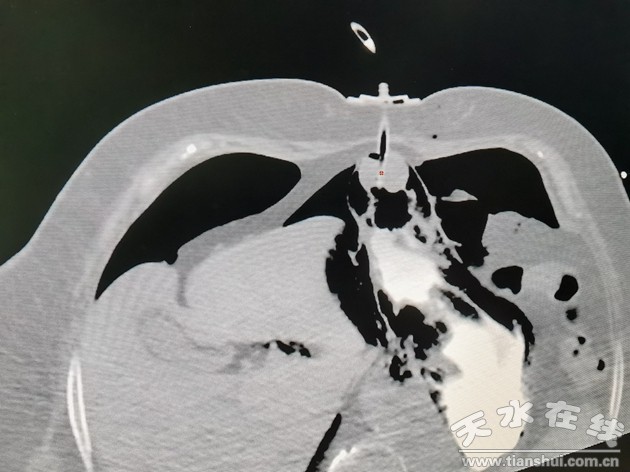

——市四院成功開展天水地區(qū)首例CT引導(dǎo)下經(jīng)皮胃造瘺術(shù)(PRG)

近日,天水市四院收治了一名因食管癌造成食道梗阻不能進(jìn)食進(jìn)水一月有余的患者。其胃鏡檢查顯示距門齒約26cm處見食管環(huán)周腫物引起食管管腔狹窄,內(nèi)鏡無法通過,不能放置胃管。因患者無法進(jìn)食導(dǎo)致身體日益消瘦,重度營(yíng)養(yǎng)不良。

經(jīng)腫瘤內(nèi)科、普外科、腫瘤外科、放射科多學(xué)科會(huì)診討論后,由放射科介入團(tuán)隊(duì)在CT引導(dǎo)下開展胃造瘺術(shù),此手術(shù)局部微創(chuàng),無疼痛,過程順利。術(shù)后患者恢復(fù)情況良好,進(jìn)食狀態(tài)也得到了極大改善,術(shù)后24小時(shí)可正常經(jīng)胃導(dǎo)管打注食物。